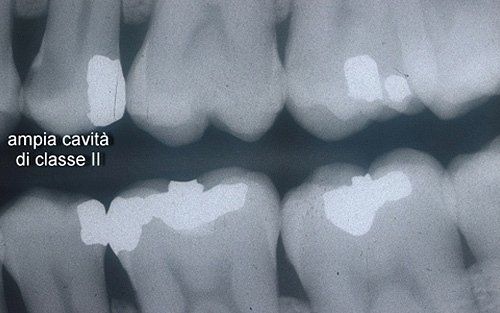

La carie non è visibile, ma il paziente avvertiva una forte sensibilità sul dente premolare

La radiografia mostra la presenza di una ampia cavità di classe II (area scura in prossimità della scritta)